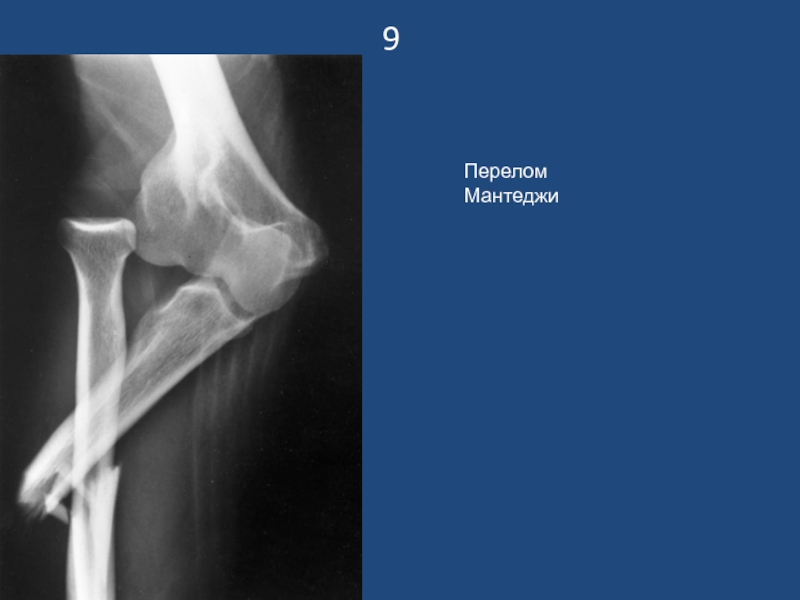

Слайд 109

Перелом Мантеджи

9Перелом Мантеджи